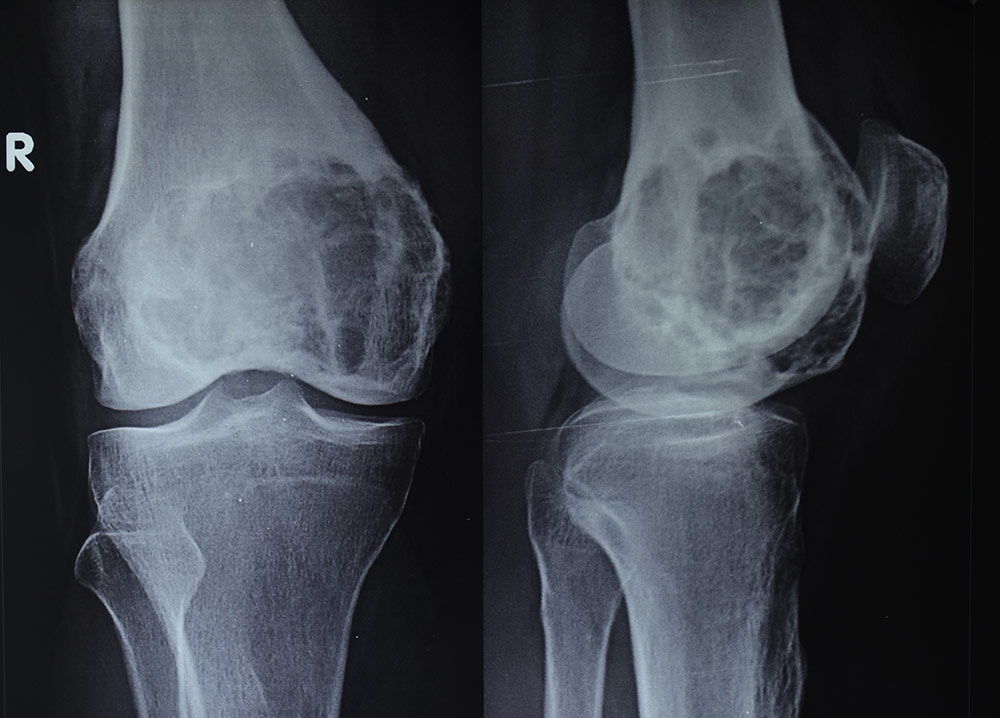

Рентгеновские снимки доброкачественных опухолей костей